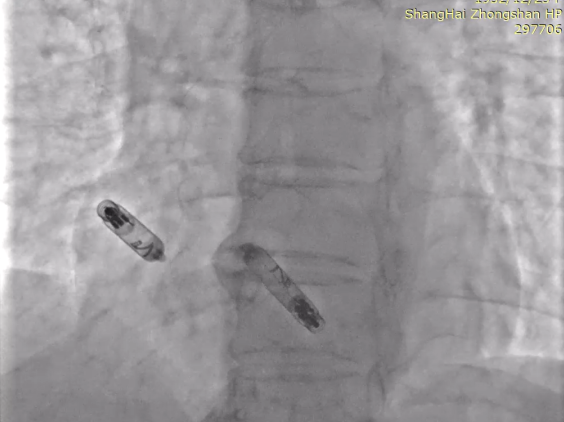

手术继续,通过猪尾造影提示植入目标位点后,优先植入心室VR,作为备用起搏,随后植入心房AR,标准流程释放无导线起搏器后,配对Aveir™ AR及VR,程控为DDD模式。

最终植入影像:

RAO30

LAO30